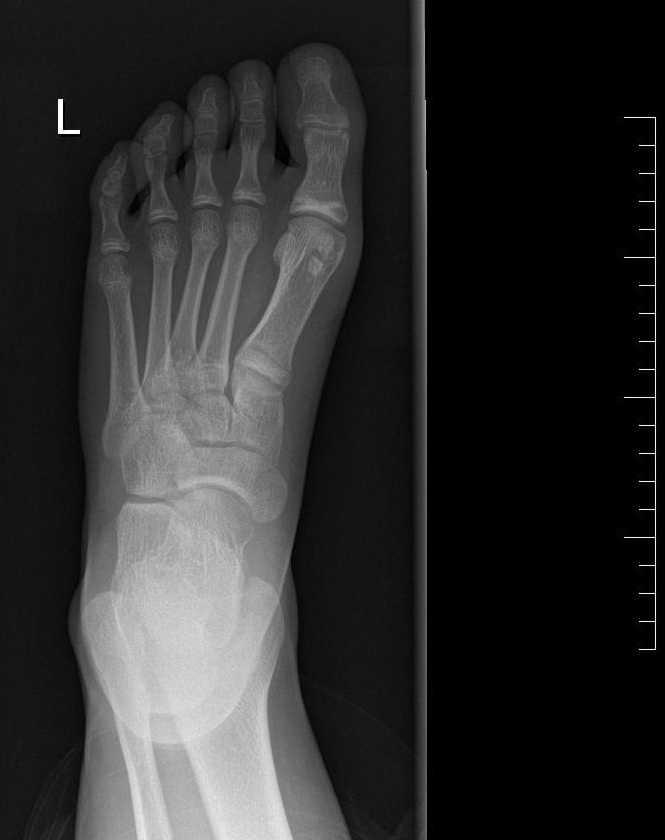

Paciente de 11 años que acude a Urgencias por dolor en el pie izquierdo de 6 meses de evolución, junto con inflamación de este en las últimas 24 horas. No guarda relación con traumatismo ni con sobreesfuerzo físico. A la exploración física, presenta dolor a la palpación en la articulación metatarsofalángica del primer dedo, con movilidad conservada. Se realiza radiografía de la extremidad (Figura 1 y Figura 2).